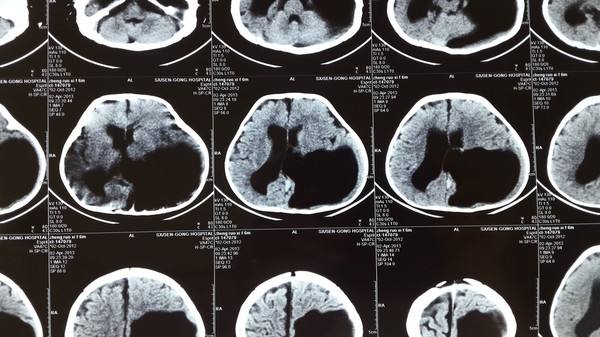

3.外伤导致的大脑受损

外伤导致大脑受损形成瘢痕之后也可以引起癫痫。常见的是车祸后、脑出血后出现癫痫。

这个跟孕期吃不吃羊肉也没有关系